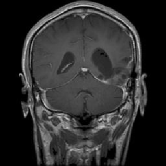

4.1.6 Brain MRI

Brain tumors pose significant health challenges, often impacting critical functions such as vision, balance, and cognition. Early detection is crucial for improving patient outcomes and quality of life. Through MRI scans, different conditions of the brain can be visually detected. The selected brain tumor dataset 666https://www.kaggle.com/datasets/sami009mr/brain-tumor-dataset contains 3,362 images across four categories: glioma, meningioma, pituitary tumors, and normal brains. Images illustrating the three aforementioned classes can be found in Fig. 7.

Table 1 provides a detailed summary of the datasets used in this study, highlighting the total number of images in each dataset, the distribution between training and testing sets, and the specific classes represented. Each dataset corresponds to a particular medical imaging domain with distinct classes relevant to diagnosing specific conditions. Also, Fig. 9 presents a representative image from each dataset, allowing for a visual comparison of the diverse tones, patterns, and textures present across the datasets. Such diversity in visual characteristics highlights the need for a robust model that can handle all image characteristics.